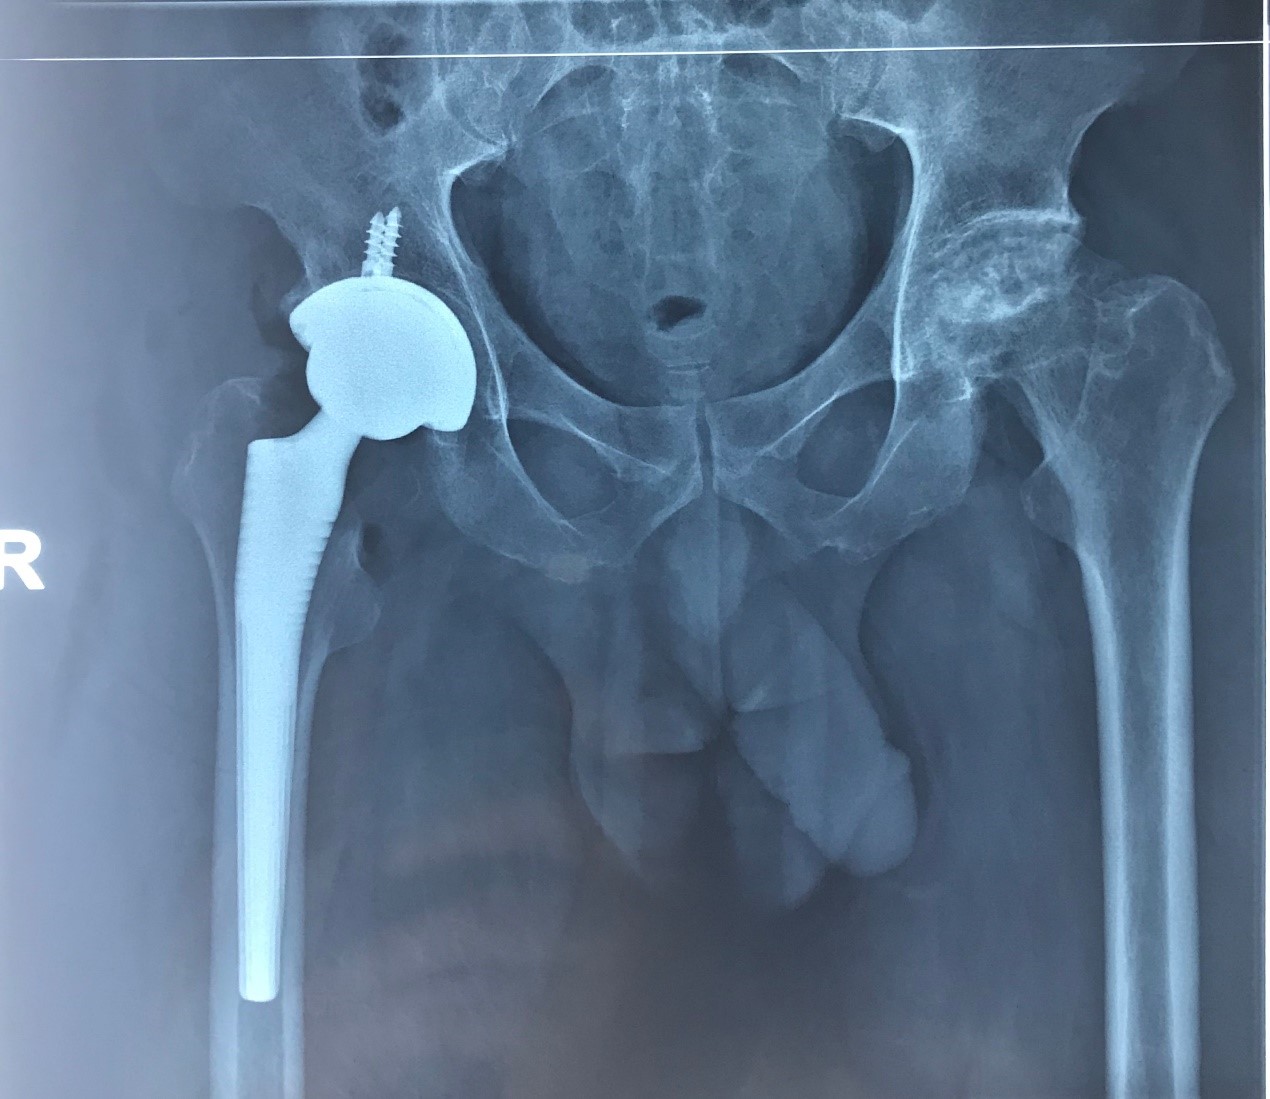

Ⅳ期:股骨头坏死的晚期,行走困难,甚至只能坐轮椅。X片检查不仅股骨头塌陷,髋臼也有一些软骨的磨损,关节间隙变窄,髋关节炎也就出现了。

Ⅲ期晚期的高龄患者,或者已经进入Ⅳ期的患者,就只能采用关节置换的方法进行治疗了。

(4)接受髋关节置换的患者,早期限制部分动作,不能早期下蹲、做剧烈的运动。